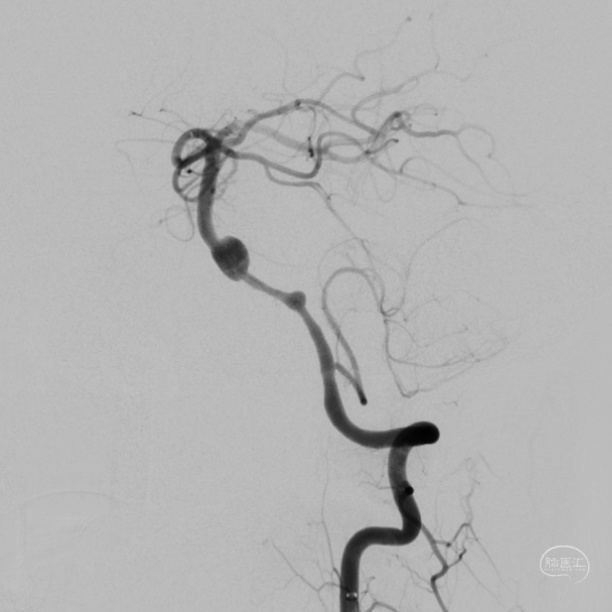

DSA:

3D重建显示基底动脉下部、双椎结合部、左椎多发夹层动脉瘤: